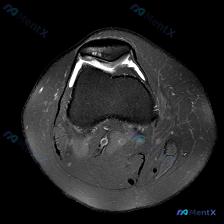

刚整理了一份膝关节MRI读片病例,分享出来和大家一起讨论一下思路。 病例基本影像信息 这是一张膝关节MRI(T2序列)轴位图像,层面覆盖膝关节前部,包含髌骨、股骨滑车及周围软组织结构: - 髌骨:骨皮质信号缺失(低信号),髓腔信号正常,皮质连续性尚可,无明显骨折线 - 股骨滑车:位于髌骨后方,可见内...

今天看到一份很有警示意义的膝关节MRI读片病例,整理出来和大家分享一下。这是一份经过髌股关节区域的膝关节轴位T2加权MRI,原始问题提示观察「软骨异常」,我们先把影像所见整理清楚: 一、病例基本影像信息 1. 髌股关节区域:髌骨前方及关节周围软组织可见弥漫性高信号,符合水肿/炎性渗出表现;髌股关节外...